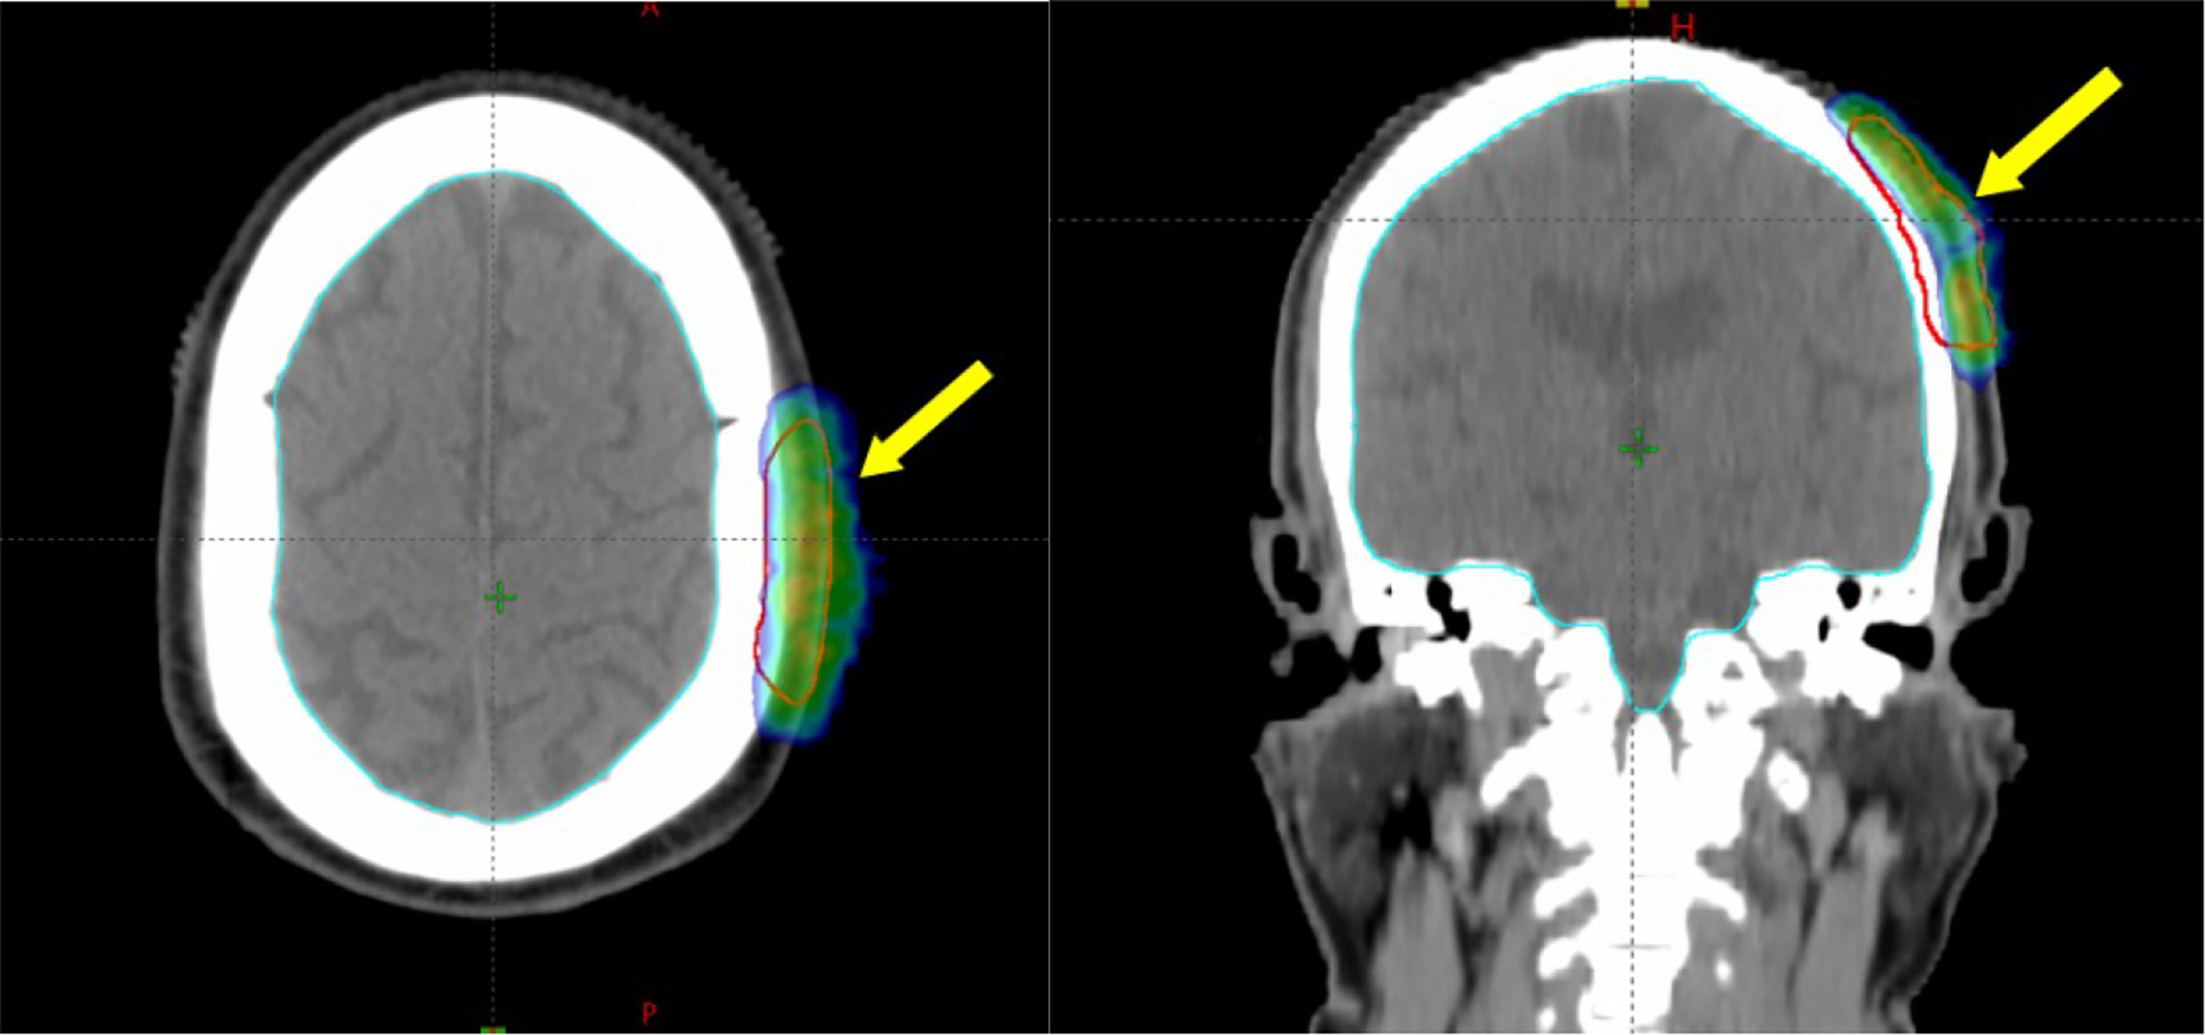

Electron-Beam Treatment Planning Process

Simulation using computed tomography (CT) was performed with the patient immobilized in the supine treatment position using a thermoplastic mask. Target volume was contoured (on the planning CT images), which included the gross scalp lesion visible on clinical examination (Figure 1A), planning CT scan, and positron emission tomography/CT (PET/CT) (Figure 2). A 2-cm uniform circumferential clinical target volume (CTV) margin was given to include the possible microscopic extension of the disease in the adjacent surrounding tissue. A 5-mm planning target volume (PTV) margin was given from the CTV to create the final target volume. Treatment planning was done on the Varian Eclipse treatment planning system using a 6-MeV nonisocentric electron beam and a gantry angle of 90° and collimator angle of 0°, with a 5-mm wet cotton bolus covering the PTV. The patient received 30 Gy in 15 fractions, 2 Gy per fraction, 5 days a week over 3 weeks. Figure 3 shows the radiation dose coverage of the target volume. Here, 99% of the gross tumor volume (GTV) and CTV received 95% of the prescribed dose. Also, 94% of the PTV received 85% of the prescribed dose (Figure 4). The patient tolerated the treatment well without any significant side effects. At the end of the treatment, the patient had grade 2 skin reactions (grading based on RTOG [Radiation Therapy Oncology Group] acute radiation morbidity) that subsided over 2 weeks.